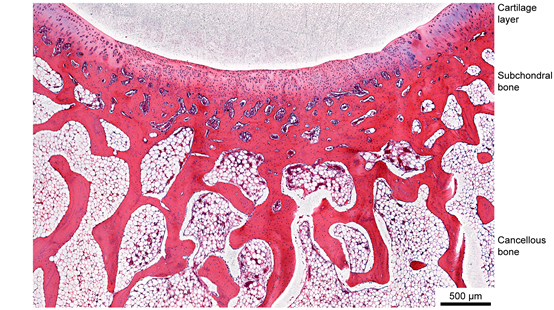

图3 再生关节软骨及其周边的组织学显微图片

丁建东教授团队运用了其所化学改性的明胶大单体gelMA水体系随温度降低呈现sol-gel转变之间的特征,并提出了“初生凝胶”的概念,即,在合适的改性程度、浓度、温度条件下,刚低于相转变点所形成的水凝胶具有显著的非牛顿流体行为,呈现强烈的剪切变稀和自修复能力,由此解决了挤出成型中方便挤出和保持塑型的两难问题,进一步将物理凝胶化和化学凝胶化相结合,获得了较为理想的交联明胶GelMA水凝胶多孔支架。调节3D打印的梁间距,制备了一系列双层多孔水凝胶支架。综合结合支架的力学性能、体外细胞迁移和增殖实验以及体内的兔关节软骨-软骨下骨的再生修复。研究发现在溶胀的水凝胶支架中,中等合适的孔隙能保证细胞的充分迁移、营养的充分输送并且提供必要的力学性能。优化条件下再生的关节软骨的微观结构呈现正常的组织学形态。